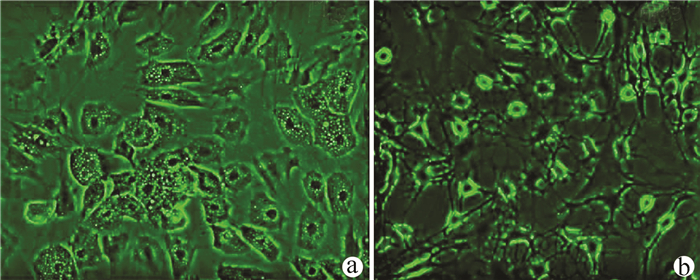

目的  了解中性胆固醇酯水解酶1(neutral cholesterol ester hydrolase 1, NCEH1)基因在肝癌组织及人肝癌细胞系中表达水平, 观察NCEH1基因敲减对SMMC-7721人肝癌细胞系增殖、凋亡、侵袭及转移能力的影响。  方法  选取2013年1月—2019年6月在暨南大学附属广州红十字会医院手术治疗的32例肝癌患者标本及对应的癌旁组织, 采用实时荧光定量PCR方法检测NCEH1基因的相对表达量。从ICGC数据库下载截至2020年9月份的肝癌样本基因表达数据, 应用R软件整理数据, 筛选出每个样本中NCEH1基因表达量, 分别采用配对Wilcoxon符号秩检验和Wilcoxon秩和检验分析肝癌与癌旁组织间的差异。采用实时荧光定量PCR方法检测NCEH1基因在SMMC-7721、Bel-7402、HepG2、Hep3B人肝癌细胞系和HL7702正常人肝细胞系中的表达水平。通过慢病毒介导的小干扰RNA(siRNA)技术构建NCEH1基因敲减的SMMC-7721人肝癌细胞系, 分为NCEH1敲减组(KD组)和阴性对照组(NC组), 以实时荧光定量PCR法检测NCEH1基因的敲减效率, 再以MTT检测实验、Annexin V-APC单染法流式细胞仪检测、划痕愈合实验、Transwell实验和Transwell侵袭小室实验检测2组SMMC-7721肝癌细胞的增殖、凋亡、转移和侵袭能力, 采用t检验对两组间数据进行统计学分析。  结果  NCEH1基因在肝癌组织中的平均表达量高于癌旁组织(本院标本Z=2.263, P=0.024, ICGC数据库U=18 768, P<0.001)。NCEH1基因在中等侵袭转移潜能的SMMC-7721细胞系中的表达量最高; 在低侵袭转移潜能的Bel-7402和HepG2细胞系中的表达水平次之, 在无侵袭转移潜能的Hep3B细胞系中的表达水平最低。KD组SMMC-7721细胞中NCEH1基因的表达水平明显低于NC组(t=11.578, P=0.000 3), NCEH1基因的敲减效率高达74.0%。较之NC组, KD组细胞生长速度明显减缓(t=32.10, P<0.001);细胞凋亡率明显升高(t=27.303, P<0.001);迁移率、转移和侵袭细胞数均明显降低(t值分别为9.51、38.123、22.331, P值均<0.001)。  结论  NCEH1基因在肝癌组织及细胞系中的表达明显升高, 且可促进肝癌细胞的生长增殖及侵袭转移并抑制凋亡, 提示其可能是一个潜在的肝癌治疗靶点。

小干扰RNA沉默甲胎蛋白基因对HepG2细胞迁移及侵袭的影响

韩伟, 魏丰贤, 张有成

2021, 37(8): 1873-1877. DOI: 10.3969/j.issn.1001-5256.2021.08.024

摘要(1252) HTML (440) PDF (2480KB)(79)

摘要:

目的  研究甲胎蛋白(AFP)对肝癌HepG2细胞迁移和侵袭能力的影响及其机制。  方法  应用合成的靶向沉默AFP小干扰RNA(siRNA)转染肝癌HepG2细胞, 分为空白对照、阴性对照组及AFP siRNA组, 各组细胞干预48 h后, 采用实时定量PCR(qRT-PCR)和ELISA法检测细胞转染后的沉默效率, Transwell小室实验检测沉默AFP基因后HepG2细胞的侵袭、迁移能力, 用Western blotting法观察沉默AFP基因的表达对上皮-间质转化(EMT)相关蛋白(N-cadherin、Vimentin和E-cadherin)、AKT和p-AKT蛋白表达的影响。计量资料多组间比较采用单因素方差分析, 进一步两两比较采用LSD-t检验。  结果  转染沉默后, 与空白对照组相比, AFP siRNA组中AFP mRNA的相对表达量明显降低(P<0.01), 抑制率达86.440%, 同时AFP siRNA组细胞上清液中AFP蛋白表达水平同样明显降低(P<0.01)。与空白对照组相比, AFP siRNA组的迁移细胞数和侵袭细胞数显著下降, 差异具有统计学意义(P值均<0.01)。沉默HepG2细胞中AFP基因的表达后, 与空白对照组比较, AFP siRNA组EMT相关蛋白E-cadherin蛋白的表达水平升高(P<0.01), 而N-cadherin及Vimentin表达水平均明显降低(P值均<0.05), 且PI3K/AKT信号通路相关蛋白p-AKT的表达水平明显降低(P<0.01)。  结论  沉默AFP可抑制肝癌细胞转移, 基于HepG2细胞株的机制研究可能与阻断PI3K/Akt通路抑制EMT相关。